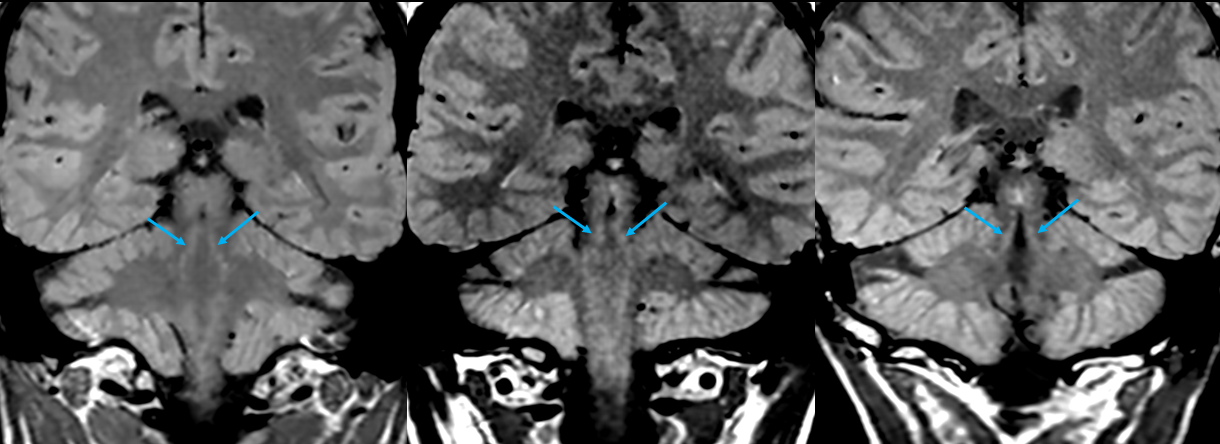

T1 mapping clearly demonstrates both elevated T1 and PD in the SN and LC compared to surrounding tissue [Fig 1]. The mean T1 value from manually drawn ROIs within the left and right substantia nigra over 2 subjects was 714 +/- 68 ms and in the locus coeruleus was 830 +/- 38 ms. This is substantially higher than the mean T1 value from ROIs in myelinated tissue neighboring the SN (572 +/- 40 ms). Thin section, PD-weighted, FSE shows clear, hyperintense signal in the SN and LC [Fig 2] whereas the T1-weighted FSE variant does not clearly visualize the SN and LC. The LC was consistently depicted in all 3 subjects and is well visualized in coronal PD-weighted FSE images [Fig 3].

Figure 2: Normal and zoomed in views of thin slice PD- plus MT-weighted FSE scans (a,b,e,f) versus T1-weighted FSE (c,d,g,h) scans. The SN (yellow arrows) and LC (blue arrows) are clearly depicted with hyperintense signal in the PD- plus MT-weighted contrast (a,b,e,f). Poor visualization of these same structures is observed in the predominantly T1-weighted scans (c,d,g,h).